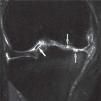

Imagen coronal en la que se aprecian lesiones profundas en el cartílago articular (flechas grises) y un cuerpo libre (flecha blanca) correspondiente a un fragmento de cartílago desprendido de los espacios señalados con las flechas grises. El alto contraste entre el líquido articular y el cartílago en secuencias ponderadas en densidad protónica con supresión grasa facilita su observación.